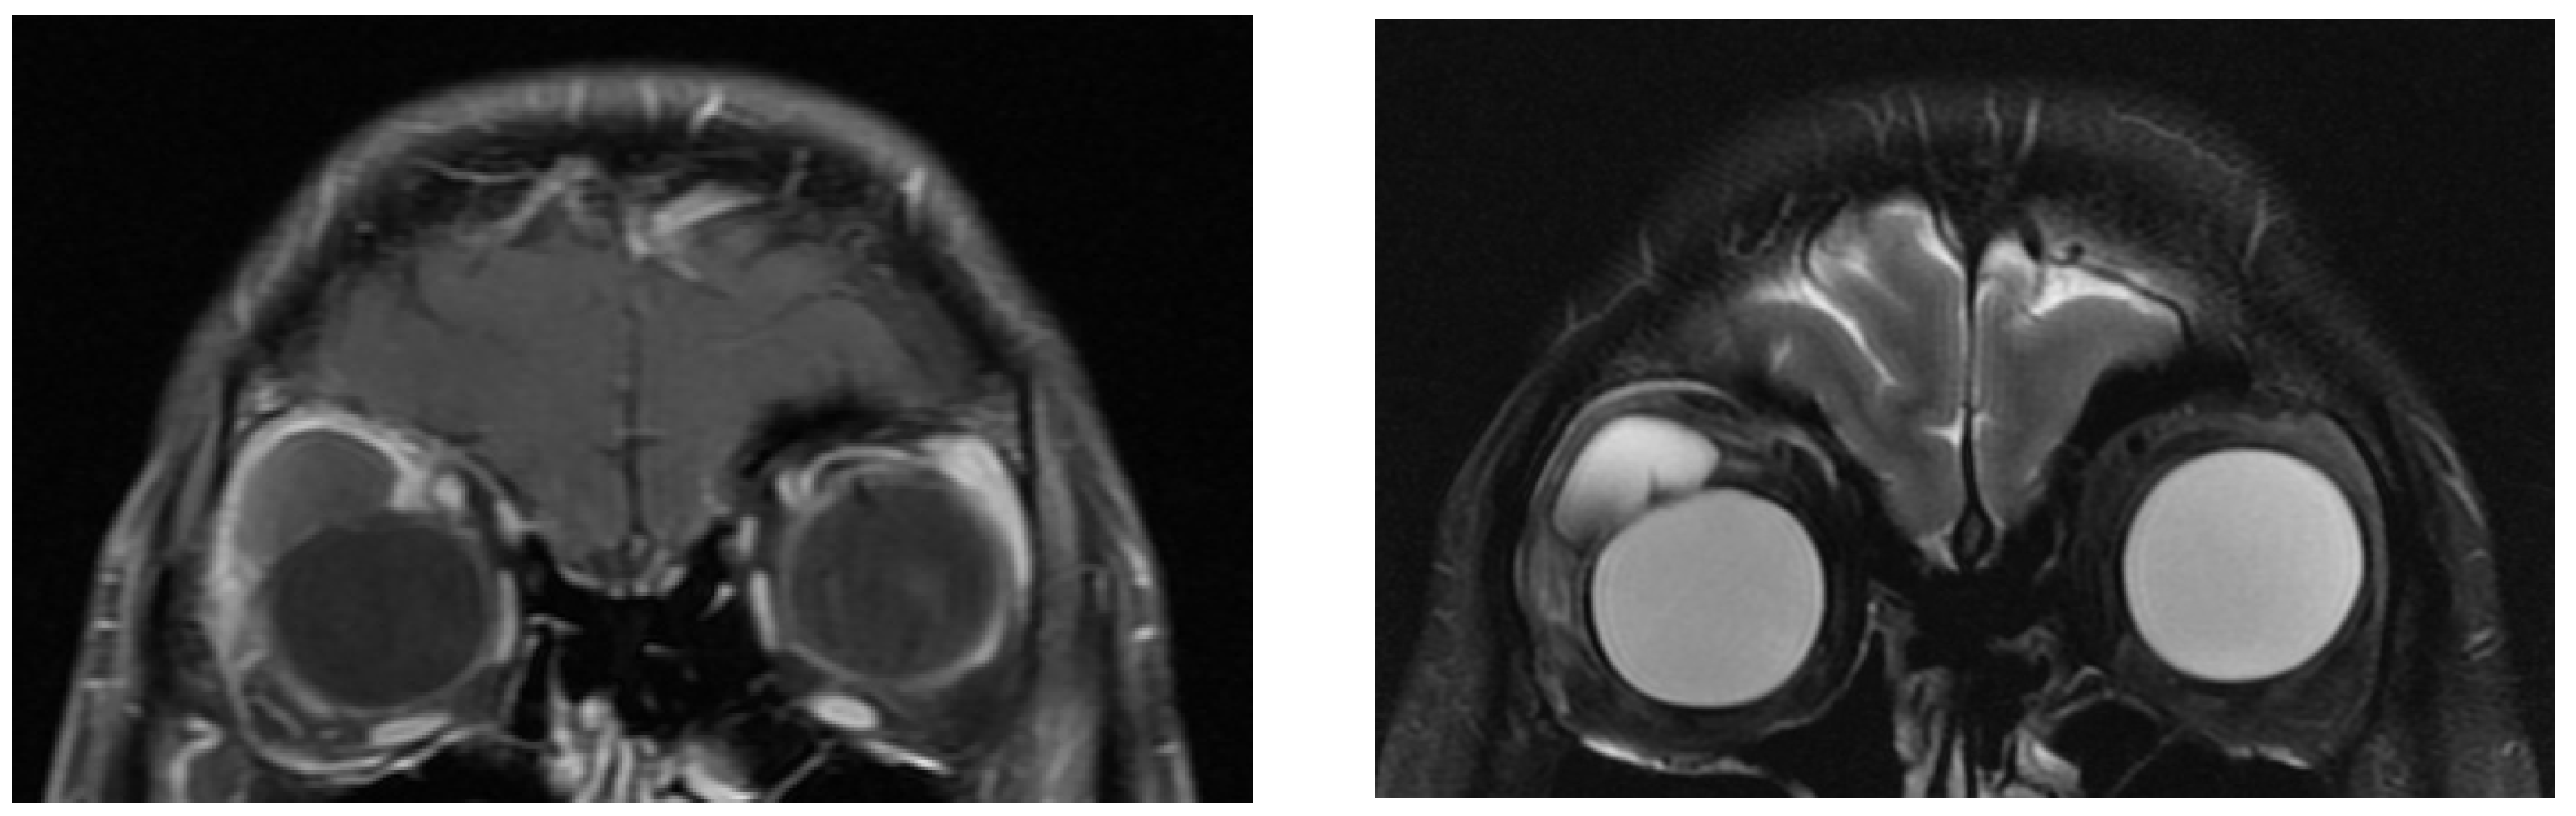

In total, we collected eleven cases; Table 1 summarizes the clinical data. One patient had bulbar atrophy before the diagnosis of swollen HSB (Figure 1). Table 2 shows the presenting symptoms of the patients. The symptoms included limitation of extraocular movement (ten eyes, 90.9%), ocular redness (eight eyes, 72.7%), ocular fullness (eight eyes, 72.7%), pain (six eyes, 54.5%), and exposed ocular foreign body (five eyes, 45.5%). Six patients (54.5%) received a correct diagnosis when referred to the medical center. Initial diagnoses other than swollen HSB included eyeball rupture (one eye, 9.1%), and orbital tumor (four eyes, 36.4%). Six patients (54.5%) had glaucoma in the diseased eyes and were treated with at least one combined form or two antiglaucoma medications before orbital HSB swelling was found. Four patients (66.7%) were male, but there was no significance of sex and glaucoma correlation according to Chi-Square analysis (p = 0.652). In the six patients with glaucoma, four cases had inadequate IOP control and one case received minimally invasive glaucoma surgery due to uncontrolled IOP one year before HSB removal. New onset of limitations of extraocular movement prompted the doctors to survey for orbital lesions. The typical CT image finding of HSB is a circumferential and homogenous mass around the globe. As this material usually swells when it absorbs water and forms a pseudocapsule around itself, CT images show an isointense signal with a vitreous and non-infiltrative lesion that deforms the eyeball. A scattered, and hyperintense signal, which corresponds to calcific change, can also be found around the swollen HSB (Figure 2). In MRI study, the HSB usually show hypointensity in T1-weighted images and hyperintensity in T2-weighted images, as these materials absorb water (Figure 3). According to the location of HSB in orbital CT, we categorized the HSB coverage into two groups: anterior-located (Figure 4) and posterior-located HSB (Figure 5). In the six patients with glaucoma, four (66.7%) showed posterior-located HSB. However, Fisher’s exact test of the relationship between the posterior-located HSB and glaucoma diagnosis did not reach clinical significance (p = 0.061).

Figure 3. MRI of hydrogel scleral buckles were hypointense in T1 (left) and hyperintense in T2 (right) images.